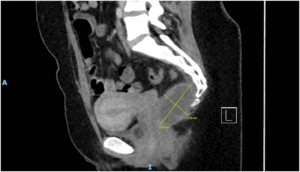

Imaging via MRI and CT demonstrated a complex, encapsulated lesion with peripheral enhancement and restricted diffusion. Multidisciplinary evaluation suggested a congenital epidermoid or duplication cyst. Given the absence of malignancy and surgical complexity, a conservative management strategy was adopted.

Figure 1: Figure 1 Duplication cyst 2025 MRI sagittal plane

Figure 2: Figure 2 Duplication cyst 2025 MRI sagittal plane

Figure 3: Figure 3 Duplication cyst 2020 Coronal plane

Figure 4: Figure 4 Duplication cyst 2020 sagittal plane

Figure 5: Figure 5 Duplication cyst axial 2020 plane post cystic aspiration

Figure 6: Figure 6 Duplication cyst 2025 sagittal plane

Figure 7: Figure 7 Duplication cyst 2025 MRI axial plane

Figure 8: Figure 8 Duplication cyst 2020 axial plane